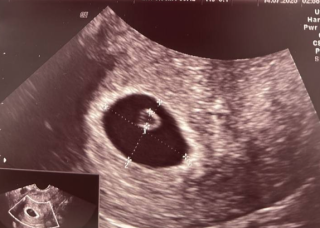

На другому УЗД побачили два плідних яйця — ембріон поділився на два. Це рідкісне, але природне явище. Утворилася одна плацента і два ембріони.

Під час першого скринінгу виявилось, що один ембріон не розвивається. Другий — активний, відповідає терміну, має гарне серцебиття. Вагітність продовжується — як здорове одноплідне виношування.